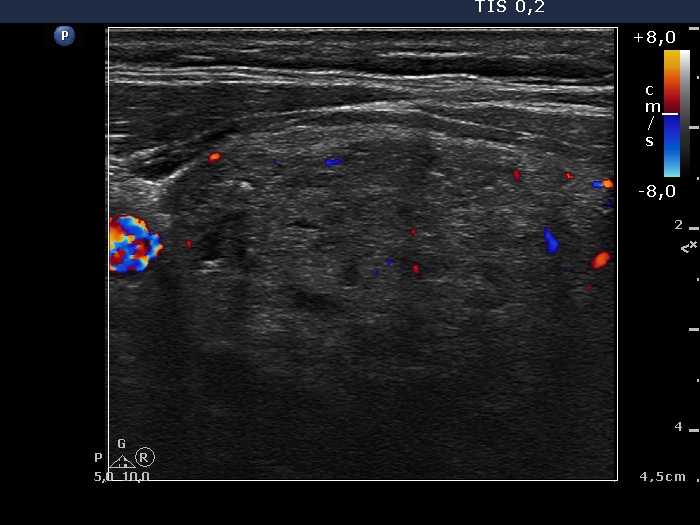

Right lobe, longitudinal scan

Right lobe, transverse scan, color Doppler mode. The vascularization is not specific.